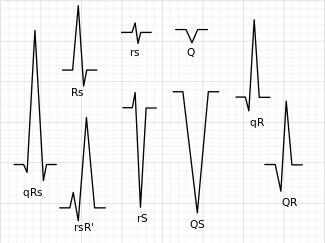

QRS complex